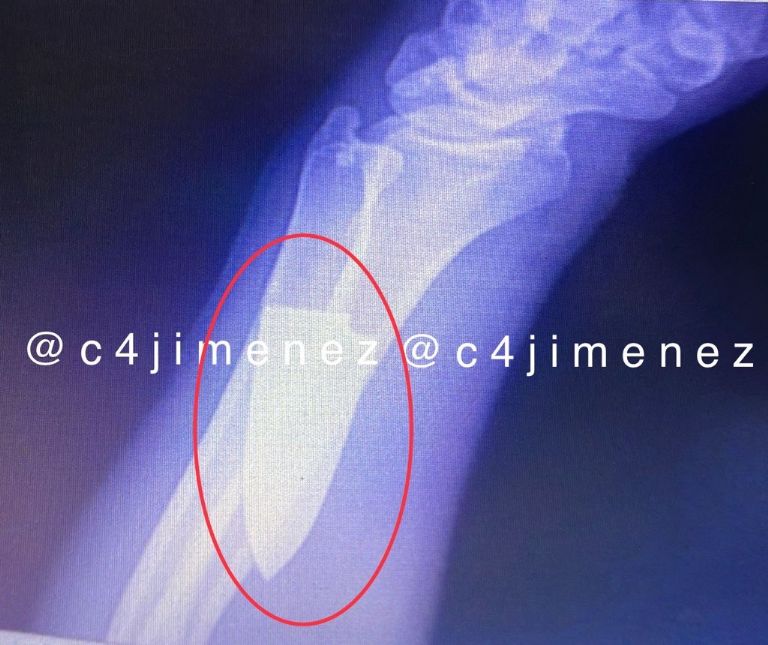

Este apuñalamiento se registró al interior de la estación Jamaica de la Línea 9 del Metro de la Ciudad de México y sucedió el pasado 16 de agosto. El responsable, un hombre de 38 años fue detenido por las autoridades, mientras que la víctima, identificado como Daniel Ordoñez, fue trasladado a un hospital, lugar donde se le atendió la herida en el brazo, pues parte del arma seguía incrustada.